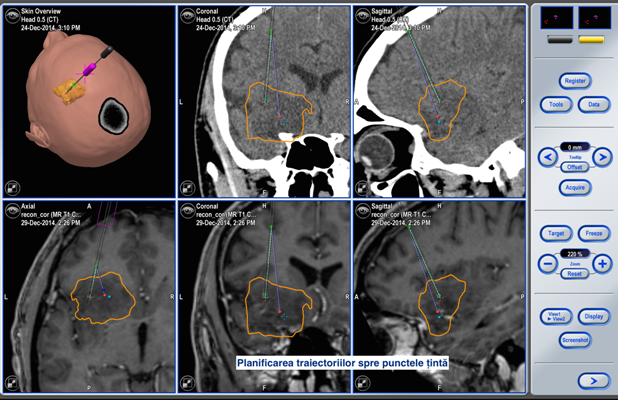

Toate aceste incomodități lipsesc în cadrul biopsiei cu utilizarea neuronavigației fără cadru stereotaxic. Astfel, procedura pentru pacient arată cât se poate de simplu. Pacientul intră în sala de operație fără cadru pe cap și iese de acolo cu procedura de biopsie realizată, localizarea și precizia biopsiei fiind confirmate pe masa de operație.

Biopsia cerebrală reprezintă o tehnică indispensabilă pentru pacienții neurochirurgicali care suferă de o patologie a creierului greu accesibilă. Metoda este absolut necesară ca etapă premergătoare, în cazul localizării proceselor patologice în zone elocvente ale creierului sau în cazul în care este nevoie de un diagnostic diferențial precis. Utilizarea sistemului nu este limitată numai la biopsie. Sistemul de neuronavigație existent în SCR permite a ghida nu numai canulele de biopsie dar și alte instrumente, în special, endoscoapele cerebrale. Acest lucru permite de a accesa într-o manieră sigură orice proces localizat în creier, iar etapa curativă sau de diagnostic poate fi realizată prin control vizual, cu ajutorul endoscopului cerebral.

Pacientul S., a beneficiat de tehnologiile existente în volum deplin. Operația a durat 2 ore. Pacientul și-a revenit după o oră de la intervenția chirurgicală, iar peste o zi a fost externat. Pentru prelevarea biopsiei a fost aleasă o porțiune de tumoare localizată la adâncimea de 13 cm de la suprafață. Locul ales a fost țintit cu precizia de 0,2mm! Acest grad de precizie este suficient pentru toate biopsiile cerebrale, iar în anumite circumstanțe, sistemul poate fi utilizat și pentru tratamentul parkinsonismului.